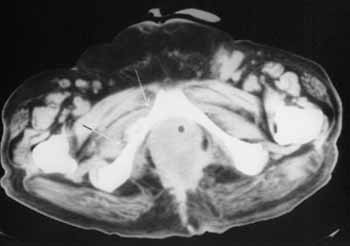

Рис. 6. Рецидив. Метастаз в правую лонную кость - деструкция с тканевым компонентом (между стрелками). Увеличение паховых лимфатических узлов с экстракапсулярным ростом слева (метастазы).